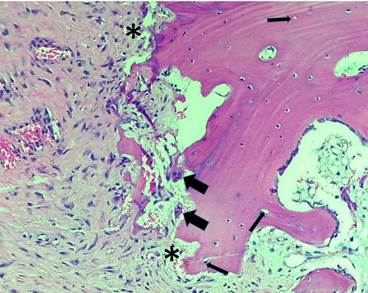

Histopathological diagnosis. The femoral head and neck surgical piece was fixed in 10% formaldehyde and sent for histological-pathological study with haematoxylin and eosin staining in the Histopathology Laboratory of the Universidad Científica del Sur. Histopathologically, a wide variety of trabecular bone necrosis was observed with limited inflammatory changes. The diagnosis corresponded to avascular necrosis of the femoral head and neck (Figures 5 and 6).

Figure 6 The bone marrow has been replaced by fibrotic marrow in an eosinophilic matrix, this tissue as a whole is partially connected to the necrotic bone (asterisks). Some multinucleated giant cells can be seen in the periphery of the matrix (large arrows). There are some empty gaps in the trabecular bone containing necrotic osteocytes (thin arrows). (Hematoxylin and eosin, 40x).

The histological findings also belonged to the expected findings in a necrotic bone affected by AVNFH 11,14. These changes were reported as empty osteocyte gaps or with necrotic osteocytes. This necrotic bone was surrounded by fibrotic bone marrow, which was disorganized and with abundant collagen fibers. An eosinophilic matrix and some giant multinucleated cells adjacent to the bone trabeculae were also identified in the marrow.